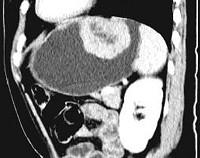

女,51岁,上腹部隐痛不适,CT检查如图,可能的诊断是 ( )A.胃癌B.胃息肉C.胃腺瘤D.胃溃疡E.胃间质瘤

问题 女,51岁,上腹部隐痛不适,CT检查如图,可能的诊断是 ( )

选项 A.胃癌 B.胃息肉 C.胃腺瘤 D.胃溃疡 E.胃间质瘤

答案 E